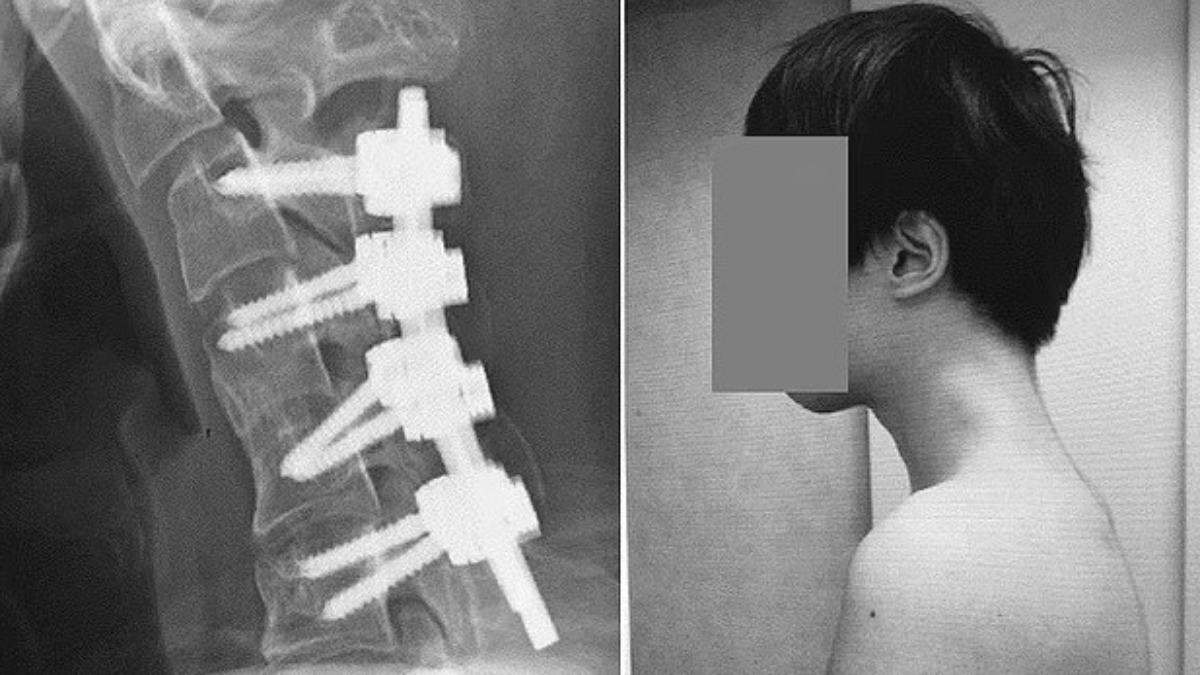

Việc cúi đầu nhìn điện thoại đã trở thành thói quen phổ biến của nhiều người hiện đại. Tuy nhiên, mới đây một trường hợp nghiêm trọng tại Nhật Bản khiến giới y khoa cảnh báo mạnh mẽ về thói quen nguy hiểm này. Một nam thanh niên 25 tuổi đã mắc phải hội chứng hiếm gặp mang tên “hội chứng đầu gục” (Dropped Head Syndrome) do trong nhiều năm liên tục cúi đầu chơi game trên điện thoại. Kết quả chụp X-quang cho thấy phần cổ của anh bị gập gần như 90 độ, kèm theo đó là phần xương cổ biến dạng và xuất hiện khối xương lồi bất thường, dẫn đến tình trạng khó nuốt, đau đớn kéo dài.

Hậu quả là cổ của anh dần biến dạng, không thể ngẩng lên được. Khi đến bệnh viện kiểm tra, bác sĩ phát hiện cột sống cổ của anh bị uốn cong tới 90 độ, kèm theo sự xuất hiện của khối xương nhô ra. Tình trạng này khiến anh gặp khó khăn trong việc nuốt và duy trì tư thế đầu bình thường.

Ban đầu, các nhân viên y tế thử điều trị bằng cách sử dụng nẹp cổ, tuy nhiên bệnh nhân cho biết bị tê liệt và khó chịu khi đeo. Cuối cùng, bác sĩ quyết định phẫu thuật: họ cắt bỏ một phần đốt sống cổ bị biến dạng cùng mô sẹo, sau đó dùng đinh vít cố định lại cấu trúc cột sống cổ.

Sau 6 tháng hồi phục, bệnh nhân đã có thể giữ đầu ở tư thế bình thường một cách dễ dàng. Trong suốt 1 năm theo dõi hậu phẫu, các chức năng như ngẩng đầu và nuốt cũng hoàn toàn trở lại bình thường.